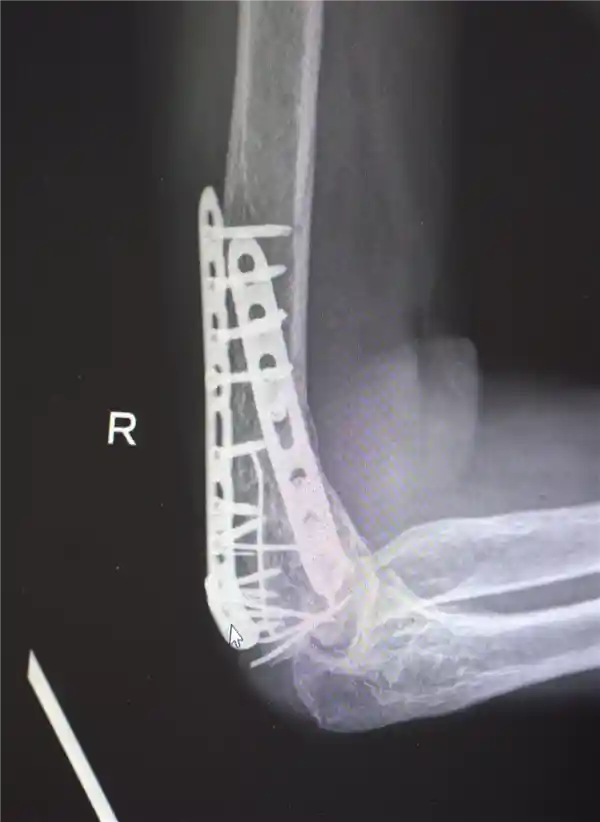

鉴于男子多处骨折,其中最严重的当属右肘部C3型粉碎性骨折,关节面及髁上严重粉碎(碎成了七块),肘关节易粘连,复位固定难度极高。

最终医疗团队运用了类似修复古董瓷器的“拼古董”复位固定技术,先将大块骨片进行拼接,再处理小块骨片,先后实施了两次手术。

部分手术后拍摄的影像